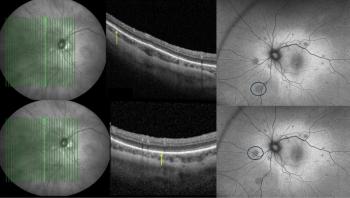

During a presentation at the EURETINA 2021 Virtual Congress, Belmonte-Grau reported that this was especially true for patients with a posterior subcapsular cataract and likely the result of needle-induced trauma to the posterior capsule during injection. Belmonte-Grau is from the Hospital Universitario de la Princesa, Madrid.

The investigators identified 20 eyes with a posterior subcapsular cataract (24.10%), 3 eyes (3.60%) with poor dilation, 2 eyes (2.40%) with mature cataract, and 1 eye (1.20%) with pseudoexfoliation syndrome.

“PCR occurs more frequently during cataract surgery in patients who were treated previously with intravitreal injections and especially those with a posterior subcapsular cataract, probably caused by needle-induced trauma to the posterior capsule during injection,” she concluded. “We emphasize thorough evaluation of the cataract preoperatively in these patients. A large majority of the complications had to be treated with vitrectomy, so this eventuality must be included in the informed consent and the information provided to patients.”